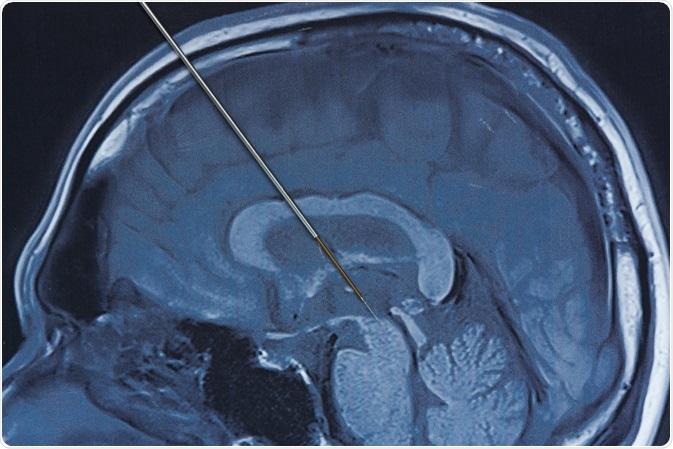

Microelectrode

Image Credit: Teeradej/Shutterstock.com

Using a microelectrode is a common method to measure oxygen consumption. A microelectrode is a biopotential electrode with an ultra-fine tapered tip. It is either inserted directly into a tissue, or an array of microelectrode needles can be placed against a tissue.

There are some drawbacks to the microelectrode method. A surface measurement can provide oxygen tension histograms over a wide field, but identification of the recording site is limited by the presence of the opaque electrode. Obtaining measurements at different sites in the field is difficult due to constant recalibration caused by the electrode having to be removed each time to take a new measurement.